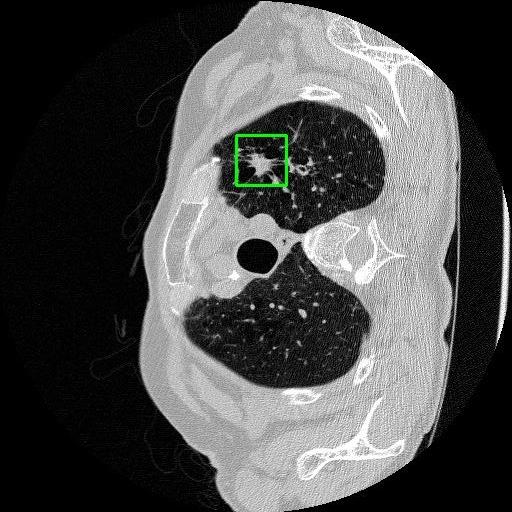

We developed an AI-based system using deep learning models for analyzing lung CT scans to detect and classify pulmonary nodules. We chose the YOLOv11 architecture for its enhanced object detection capability and adapted it specifically for medical imaging, incorporating pixel-level precision and severity classification.

Classification into three severity levels with colored bounding boxes.

Successfully built and deployed an AI model (YOLOv11) capable of detecting lung nodules in CT scans with high accuracy and real-time performance.

Designed a severity classification system that categorizes nodules into null, moderate, and severe using colored bounding boxes, assisting in rapid clinical decision-making.